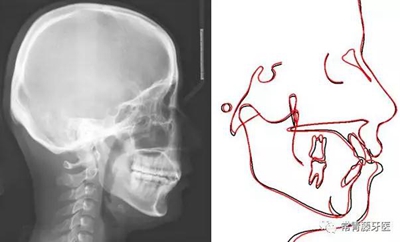

影像學檢查

頭影測量顯示上下頜骨發(fā)育不足,且呈現(xiàn)骨性Ⅱ類。

術(shù)前術(shù)后描記圖顯示上牙列整體遠移有效,表現(xiàn)為磨牙遠移及上前牙內(nèi)收(黑色術(shù)前,紅色術(shù)后)。